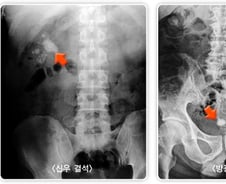

'출산의 고통만큼 극심한 통증'으로 응급실에 실려 와야 하는 병이 있다. 바로 '요로결석'이다. 땀을 많이 흘리는 여름철에 가장 흔한데, 건강보험심사평가원에 따르면 2023년 요로결석으로 병원을 찾은 환자(33만5628명) 가운데 7월(4만4419명)과 8월(4만8468명)에 가장 많았다. 2021년과 2022년에도 각각 7·8월이 그 해의 최대 환자 수를 기록했다. 요로결석은 콩팥·요관·방광·요도 등 '소변이 지나가는 길'에 돌이 생기는 질환이다. 한 번 발생하면 재발 위험이 높고, 출산의 고통에 빗댈 만큼 극심한 통증을 유발해, 예방과 빠른 대처가 중요하다. 인천힘찬종합병원 비뇨의학과 이장희 과장은 "여름철에는 땀 배출이 많아 체내 수분이 부족해지면서 소변량이 줄고, 소변이 농축돼 결석이 형성되기 쉬운 환경"이라며 "통증은 결석이 막는 위치에 따라 다양하게 나타나는데, 옆구리·복부 통증이 심하고, 혈뇨가 나오기도 한다"고 말했다. ━통증 방치했다간 콩팥 망가질 수 있어 ━여름에는